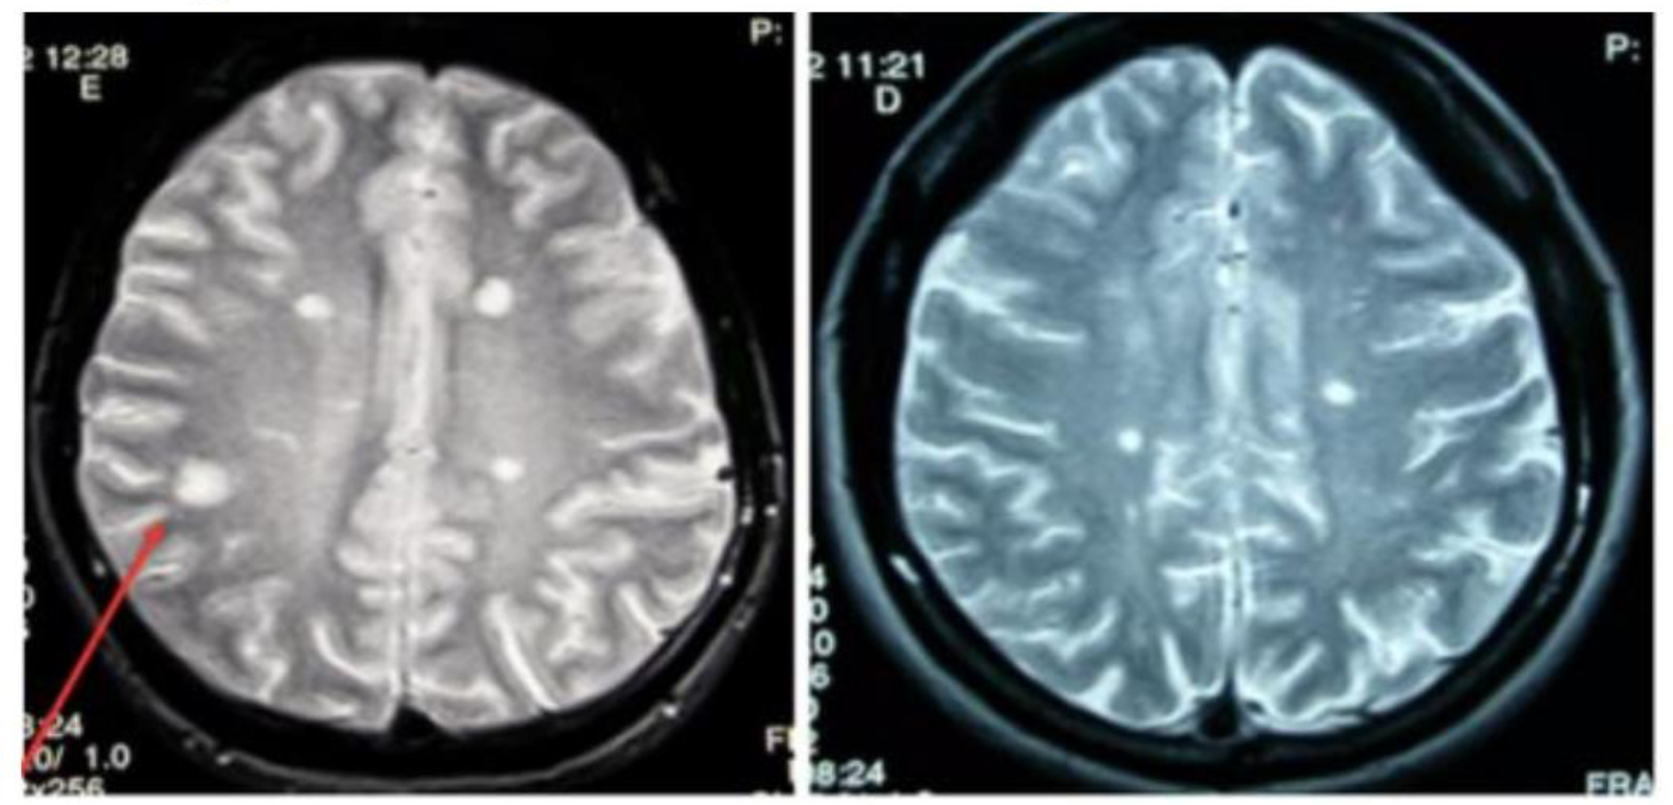

• Multiple sclerosis (MS) is a chronic autoimmune disorder characterized by inflammation, demyelination, and neurodegeneration within the central nervous system (CNS). It predominantly affects women and young adults, with environmental and genetic factors contributing to its onset. MS presents a wide range of neurological symptoms due to the scattering of lesions in the CNS, often leading to vision, sensorimotor, and cognitive impairments. The clinical course of MS varies, with relapsing-remitting MS (RRMS) being the most common, followed by secondary progressive MS (SPMS) and primary progressive MS (PPMS). Diagnosis is based on clinical evaluation, MRI findings, and cerebrospinal fluid analysis, with the McDonald criteria playing a key role in confirming dissemination in time and space. Current treatments, such as disease-modifying therapies (DMTs) and steroids, focus on managing relapses and reducing long-term disability. Novel therapies, including remyelination and neuroprotective agents, are showing promise in advancing care. While these medications can slow progression and improve quality of life, MS remains an incurable disease that requires ongoing research to find more effective therapies. Surgical interventions are rare but can address severe symptoms like spasticity and bladder dysfunction, contributing to an overall personalized management approach.